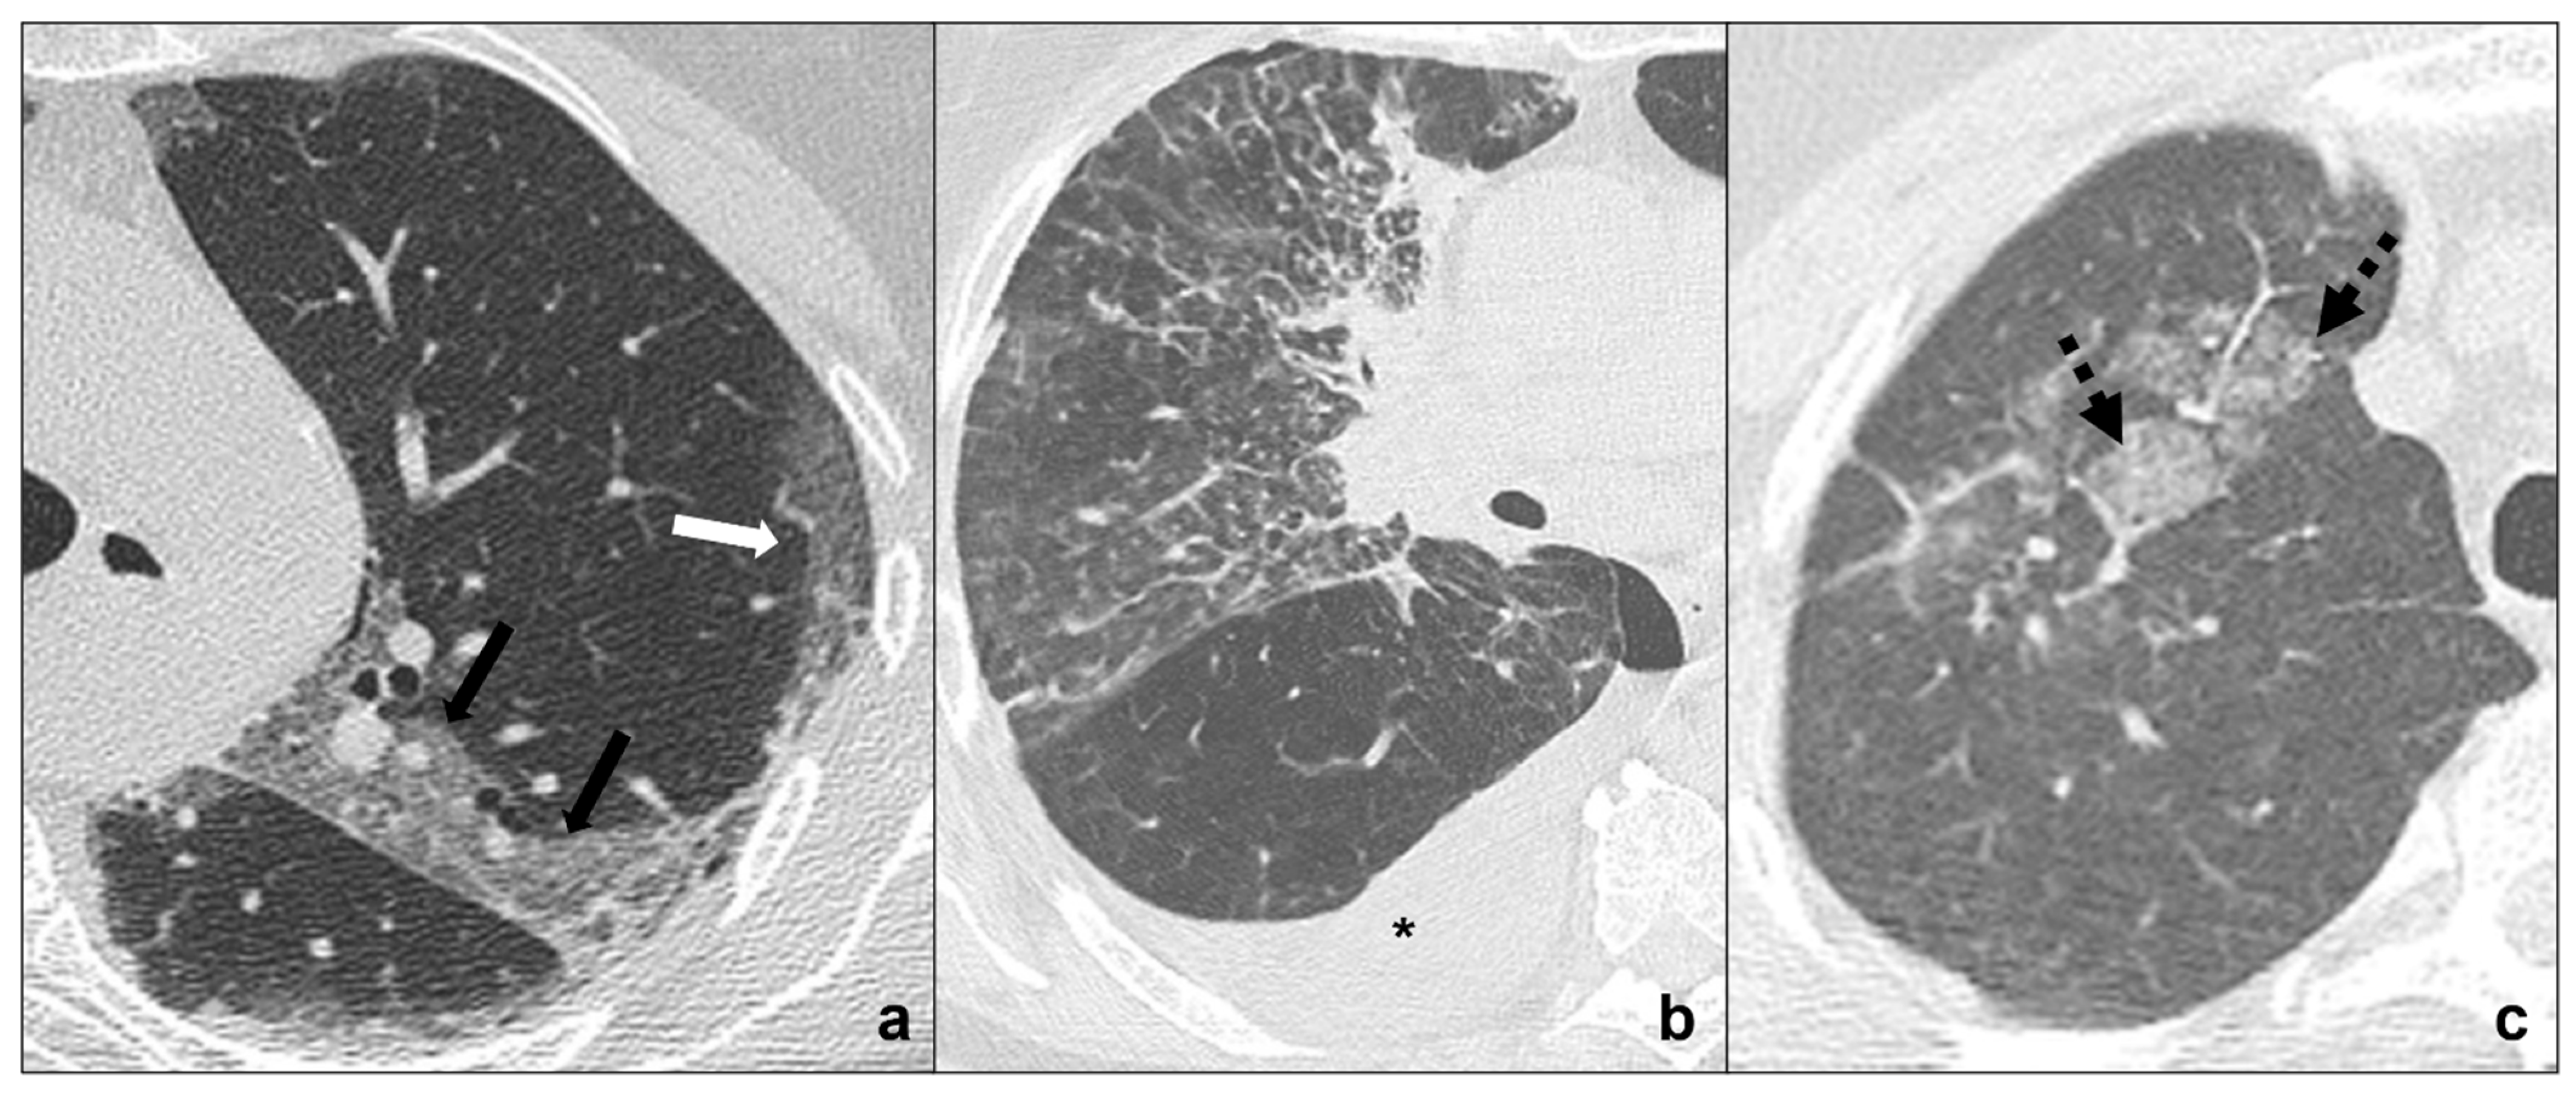

It is a minimally-invasive lepidic-growing tumor that may be seen as a focal ground-glass opacity surrounding a nodule ≤5 mm on CT scan [43,44]. The presence of focus or foci of invasive adenocarcinoma may help distinguish MIA from AIS [36], but the diagnosis can only be made after a complete histologic review [34,36] (Figure 4b).

Figure 4.

(a–f) HRTCs showing differential diagnoses of COVID-19 pneumonia stage 2–3/consolidations with ground-glass/crazy paving opacities. The transition between stage 2 and 3 of COVID-19 pneumonia is characterized by confluent consolidative foci (black circle in (a)) in extensive areas of ground-glass (white arrow in (a)) and/or crazy paving opacities (black arrow in (a)). Differential diagnosis with adenocarcinoma should include: minimally invasive adenocarcinoma presenting as a ground-glass area surrounding a solid nodule < 5 mm (dotted black arrow in (b)); invasive non-mucinous adenocarcinoma in which the nodule is >5mm and there is a small surrounding area of ground glass (dotted white circle in (c)); and invasive mucinous carcinoma, in particular the multicentric carcinoma (d) which presents as bilateral intraparenchymal or subpleural consolidations (dotted white arrows in (d)) surrounded by areas of ground-glass/crazy paving (black arrows in (d)) co-existing with extensive areas of ground-glass and crazy paving opacities (black arrows in (d)). Additional findings such as lymphadenopathies (black asterisks in (e)) may guide differential diagnosis. In (f), HRTC of patients presenting with chemotherapy induced organizing pneumonia characterized by extensive areas of ground-glass opacities (white arrows in (f)) coexisting with ill-defined consolidations (dotted black circle). Lungs: mean window with 1500 HU; mean window level −600. Mediastinum: mean window with 350 HU; mean window level 50 HU.

3.3.2. INMA (Invasive Non-Mucinous Adenocarcinoma)

Among the variants there is lepidic adenocarcinoma, which appears as a solid nodule (>5 mm) with a small surrounding ground glass opacity indicating lepidic growing on CT [26,38]. The size of focus of the invasive carcinoma being >5 mm has been shown to be an effective way to distinguish INMA from AIS and MIA [45] (Figure 4c).

3.3.3. IMA (Invasive Mucinous Adenocarcinoma)

This is a focal or multicentric invasive lepidic-growing mucinous adenocarcinoma with a variety of different presentations from solid to non-solid on CT scan depending on mucin production [43,44] (Figure 4d).

Clinics and anamnesis are extremely important because tumors are often asymptomatic in the early phases or may show long-lasting symptoms. Radiological features for differential diagnosis of MIA, INMA, and IMA with COVID-19 pneumonia [18,34,36,46] (Figure 4a–e) include:

- tumors are generally focal entities and appear as ground-glass opacities (atypical adenomatous hyperplasia likely being ≤5 mm, adenocarcinoma in situ generally being bigger, even measuring ≤3 cm), or ground-glass opacity surrounding a nodule (≤5 mm in minimally invasive adenocarcinoma and >5 mm in lepidic predominant adenocarcinoma);

- even if tumors are multicentric, such as invasive mucinous adenocarcinoma, they tend to grow even after antibiotic or anti-inflammatory treatment;

- additional findings such as cysts (cystadenocarcinoma);

- cleavage invasion;

- lymphangitic carcinomatosis (Figure 3b);

- mediastinal lymphadenopathies (Figure 4e) and pleural effusions.

This is common after therapeutic irradiation of intrathoracic and chest wall malignancies [52] and can be divided into acute RILD (≤6 months from completion of therapy) (Figure 2c and Figure 3c) and chronic RILD (up to 2 years from completion of therapy) [51,53] (Figure 6c,d).

Figure 6.

(a–d) Chest CTs showing differential diagnoses of COVID-19 pneumonia stage 4/absorption phase characterized by parenchymal bands (black-bordered white arrows in (a). Differential diagnoses generally include chemotherapy-induced lung disease (b) and radiation-induced lung disease (c,d). In (b), HRTC of a patient presenting with OP showing pulmonary parenchymal ill-defined bands and consolidations during a chemotherapy cycle (black arrows in (b)); in (c,d), chest CT of a patient who underwent radiotherapy for an apical lung cancer, showing an extensive mass with irregular margins, pleural and mediastinal retraction striae (black dotted arrow) and with some calcification within (dotted white arrows) in the field of radiation. Lungs: mean window with 1500 HU; mean window level −600. Mediastinum: mean window with 350 HU; mean window level 50 HU.

Radiations may induce abnormal pulmonary reaction resulting in linear fibrotic parenchymal bands to massive consolidations causing retraction on pleural/parenchymal tissue and mediastinum, bronchiectasis, and architectural distortions. These areas are generally located in the radiation field boundaries [53].

Anamnesis of radiation exposure and comparison with previous CT scans are necessary for a correct differential diagnosis. Radiological features for differential diagnosis between RILD and COVID-19 pneumonia [51,53]:

- parenchymal lesions located within radiation field boundaries, in particular ground-glass or crazy-paving opacities in acute RILD and consolidations with calcification foci in chronic RILD;

- additional findings such as nodules, atelectasis, and tree-in-bud, more common in radiation pneumonitis;

- evidence of fibrosis, traction bronchiectases, volume loss, architectural distortion, and ipsilateral displacement of mediastinum during the chronic stage;

- pleural effusions in the early stage and pleural thickening in the chronic stage.